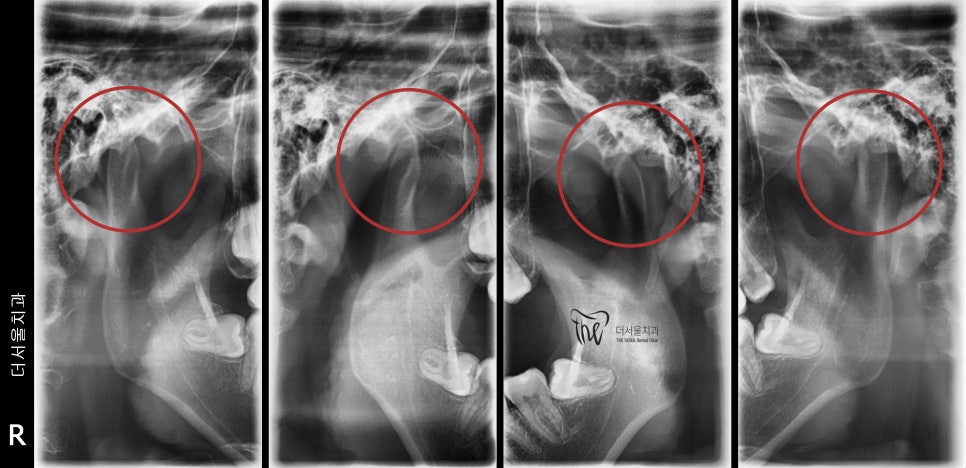

먼저, 턱관절 사진을 보여드릴게요.

표기를 해 둔 곳의, 뼈 단면을 보면

많이 폭경이 얇아진 것을 볼 수 있습니다.

원래부터 그랬을까요?

아뇨, Open bite 를 갖고 있기 때문에

나타난 부작용 중에 한가지인, 마모 현상입니다.

원래는, 통통했을겁니다.

근데, 본인이 가지고 있는 교합관계에 따라서

이러한 문제들이 나타난 겁니다.

아마, 시간이 더 흘러서 제때 치아교정 을

받지 않았더라면 그때는 구강내과의 도움을 받아

전혀 다른 영역에서 치료를 하게 될 수 있죠.

뭐 예를들어서,

- Anterior disc displacement without reduction 과 같은 비정복성 관절원판 내장증

같은 증세들이 나타날 수 있습니다.

결국, 만성질환으로도 이어질 가능성이

농후했었던 상황이였습니다.